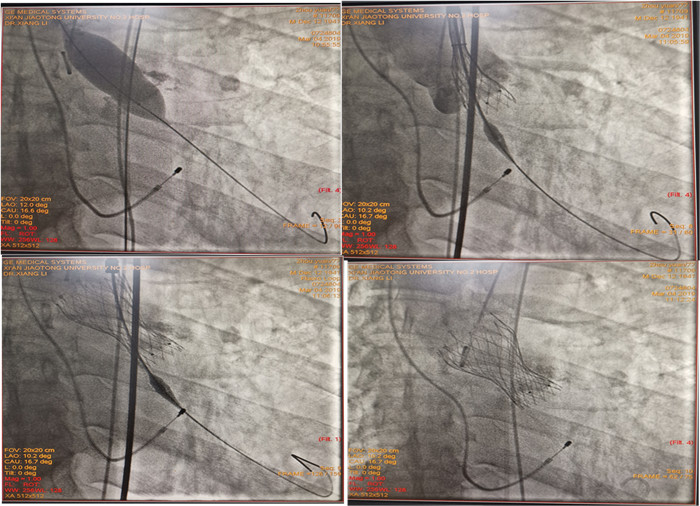

3月4日上午,介入导管室集结了我院多个科室的专家团队为手术保驾护航,介入室徐光技师负责DSA造影机的控制;超声室金鑫医生全程经食道心脏超声监测;麻醉科赵静医生负责全麻与压力测定;急诊科张正良医生ECMO团队、体外循环常丽医生及手术室人员均在场为临时转为开胸手术的紧急情况随时待命。由裴斐教授和相里伟医生等医护人员组成的心外科团队负责手术,主动脉根部造影、右心室起搏电极放置、导丝顺利通过窄至“一线天”的主动脉瓣口,球囊扩张严重钙化的瓣膜、最后通过右侧股动脉途径精确定位成功植入Venus-A生物瓣膜(图2图3),所有步骤都按计划顺利进行,即刻测量跨主动脉瓣压力阶差显著下降(由术前的120mmHg降至20mmHg,瓣口开放面积恢复正常)。历时约1.5小时,未出现明显并发症,TAVR手术圆满结束。术后第二天患者下床活动,无不适症状(图4图5)。

(图2)手术进行中

(图3)术中主动脉瓣球囊扩张及人工瓣膜的释放